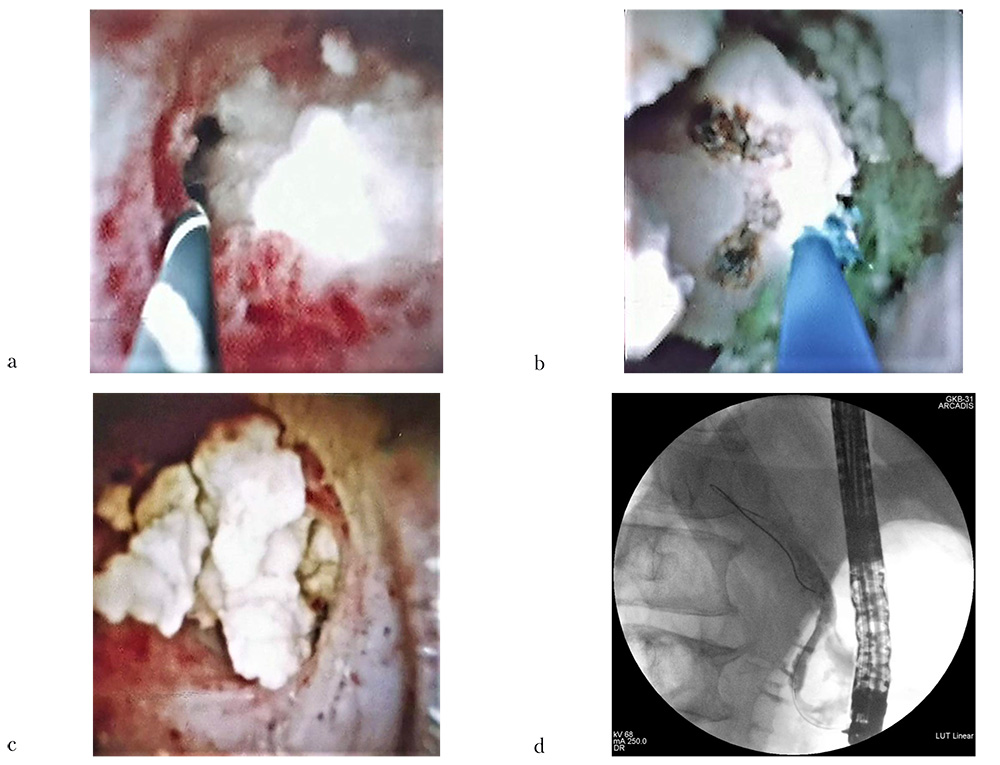

Рис. 7. Эндосонография поджелудочной железы конвексным эхоэндоскопом — в просвете расширенного вирсунгова протока (указан стрелками) крупный конкремент с яркой акустической тенью (отмечен звездочкой)

На 4-е сутки после первичного вмешательства пациент был оперирован повторно. После проведения аппарата Spy-Glass DS II фирмы Boston Scientific (США) в просвет ГПП при помощи тулиевого суперимпульсного фиброволоконного лазера FiberLase U2 с использованием лазерного волокна диаметром 400 микрон при безопасных настройках частоты и средней мощности от 60 до 100 Гц и от 6 до 10 Вт соответственно при энергии в импульсе 0,1 Дж был разрушен поверхностный слой конкремента в режиме «Распыление» (рис. 9b). После этого выполнена фрагментация основного «ядра» вирсунголита в режиме «Попкорнинг» с постепенным увеличением параметров частоты и средней мощности с 40 до 60 Гц и с 8 до 12 Вт соответственно при энергии в импульсе 0,2 Дж (рис. 9c).

При этом камень был полностью фрагментирован, что позволило в дальнейшем санировать просвет вирсунгова протока с помощью корзинки Дормиа, ревизионного баллончика и промывания стерильным физиологическим раствором. При выполнении контрольной ретроградной панкреатикографии и пероральной транспапиллярной панкреатикоскопии ГПП был осмотрен на всем протяжении от хвоста до устья: конкрементов, а также повреждений слизистой оболочки панкреатического протока выявлено не было (рис. 9d).

Рис. 9: a — вирсунголит, занимающий практически весь просвет ГПП (эндофото); b — разрушение «поверхностного» слоя вирсунголита (эндофото); c — фрагменты разрушенного «ядра» конкремента (эндофото); d — контрольное контрастирование ГПП (панкреатикограмма)